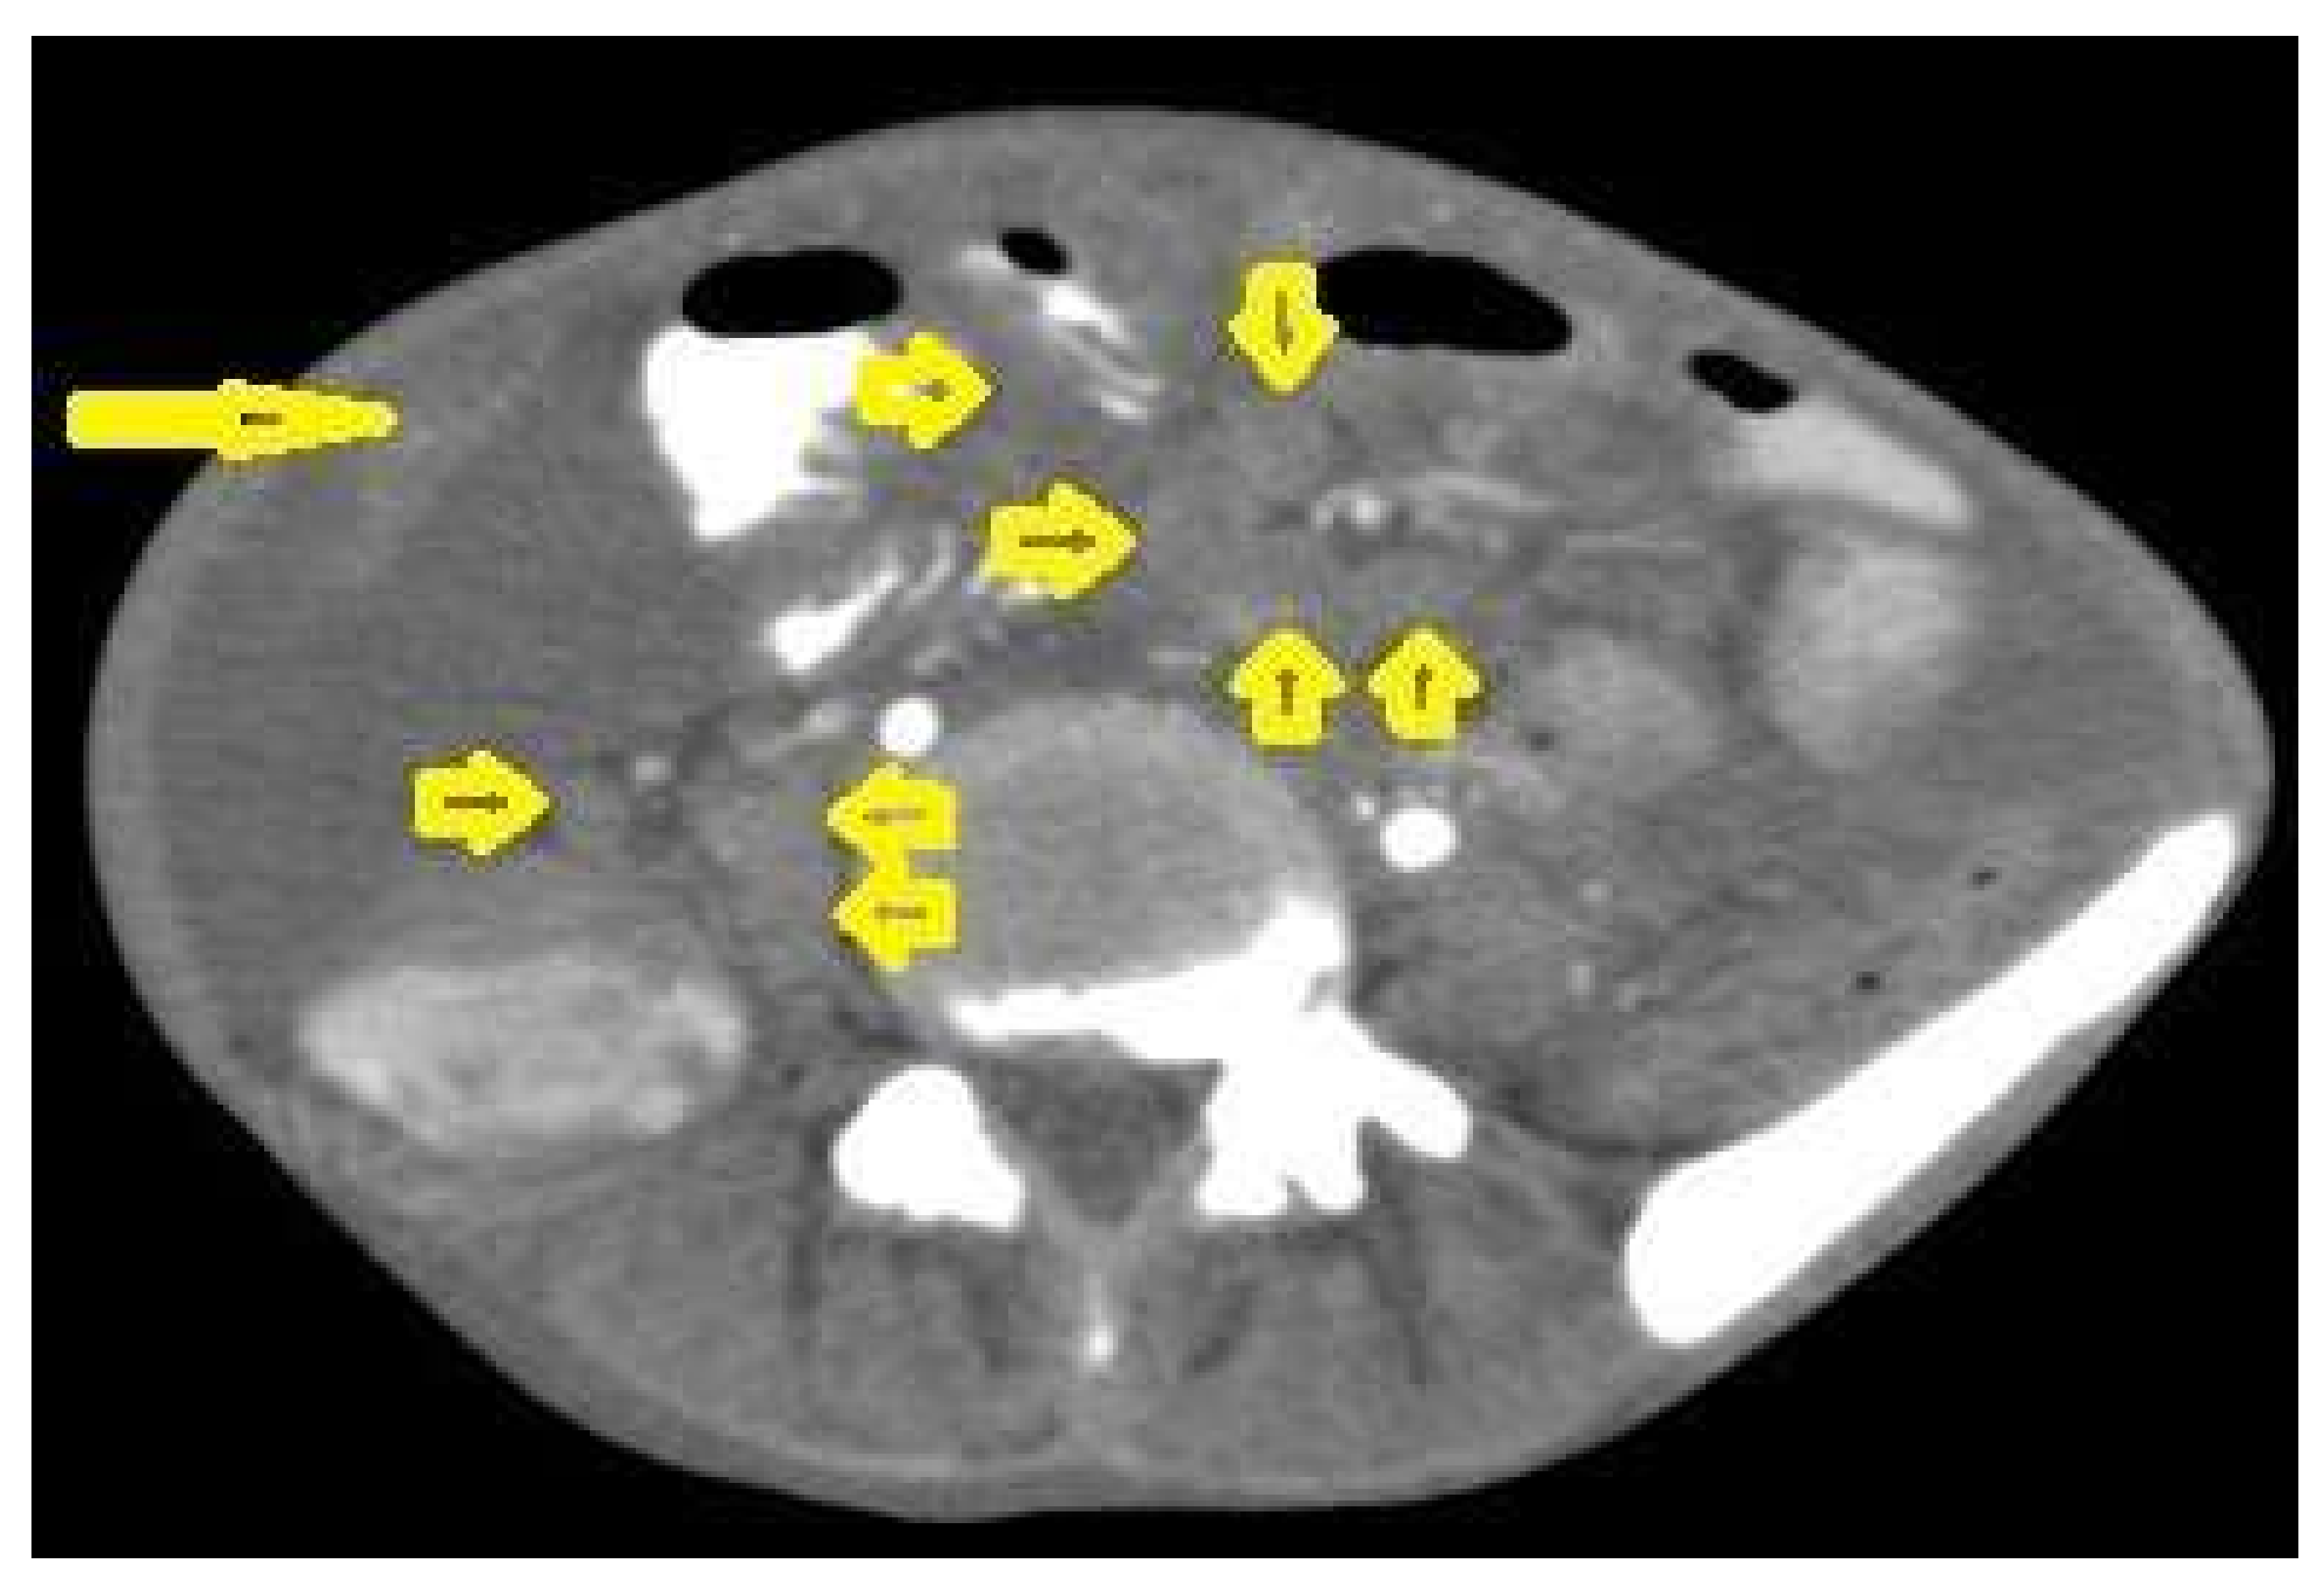

• Tuberculous lymphadenitis (Figure 20) is one of the most common radiological manifestation of abdominal TB which frequently involves multiple groups such as mesenteric and upper paraortic LNs. The majority of patients have enlarged lymph nodes with a low-attenuation center and peripheral-enhancing rim, which is characteristic of TB [45,46]. LNs may show peripheral rim enhancement, inhomogeneous, homogeneous, or no enhancement after contrast administration. Other patterns of LNs include conglomerate LNs with areas of necrosis, more than three enlarged or normal homogenous LNs in one section, or calcified LNs [45]. TB can mimic several other conditions, such as lymphoma, amebiasis, Crohn’s disease, and adenocarcinoma [47].

Figure 20. Tuberculous lymphadenitis in a 27-year-old women with cachexia, loss of appetite and cough. Axial abdominal CT image shows enlarged mesenteric, periaortic, and portahepatis lymph nodes (LNs), (short arrows) due to TB, which usually involves multiple groups, such as mesenteric and upper paraortic LNs. The image also shows relatively dense ascites and remarkable omental thickening forming cake-like mass (long arrow).